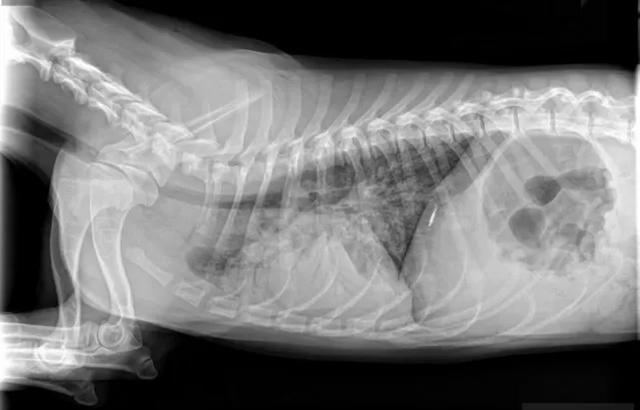

肠胃梗阻包括胃扭转、肠套叠、肠梗阻等一系列胃肠道阻塞疾病,尤其是喂了鸡骨头、误食玩具、刚吃完饭运动等情况最容易发生。

肠梗阻一般都会伴发呕吐和腹泻,有的还会便血。在初期狗狗会表现食欲不振,甚至干脆不吃不喝。该病属于危重疾病,往往都表现出几天内不进食,最终快速死亡。

如果你家的狗狗,好几天不爱吃饭,但没有呕吐拉稀等症状,可以不考虑这些疾病。如果有上述提及的症状和描述,要格外小心,特别需要注意喂食过尖锐的骨头、或者有啃咬硬质玩具习惯的狗狗。

医院检查这些疾病,X光片最常见,每次需要拍摄正侧位两张,价格240元左右。也可能涉及腹部超声,价格100~200元。